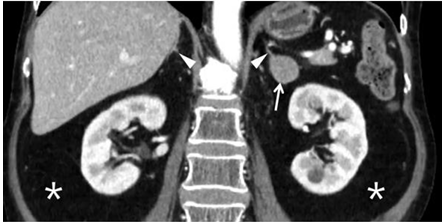

Observe atentamente a imagem e escolha a opção que completa os espaços pontilhados de forma correta. A imagem de nódulo em adrenal esquerda (apontado pela seta) identificado por_____________ sendo a função da glândula suprarrenal a ativação__________.

“A morte por dissecação da aorta torácica geralmente é causada por regurgitação aórtica aguda, obstrução de importante ramo, tamponamento pericárdico ou ruptura da aorta. As complicações decorrentes da dissecção da aorta torácica podem ocorrer no tórax ou em localização extratorácica. Mais de um terço dos pacientes com dissecção aórtica apresentam sinais e sintomas secundários ao envolvimento de outros sistemas de órgãos. O mecanismo mais comum é o desenvolvimento de isquemia secundária à obstrução de artérias ramificadas com origem na aorta, como as artérias renais. A obstrução do ramo-vaso pode ser causada por uma extensão do processo de dissecção na parede do vaso ou uma compressão direta da artéria ramo por um lúmen falso em expansão”. A imagem que segue demostra essas e outras regiões. Escolha a opção que revela a função/fisiologia da artéria aorta.